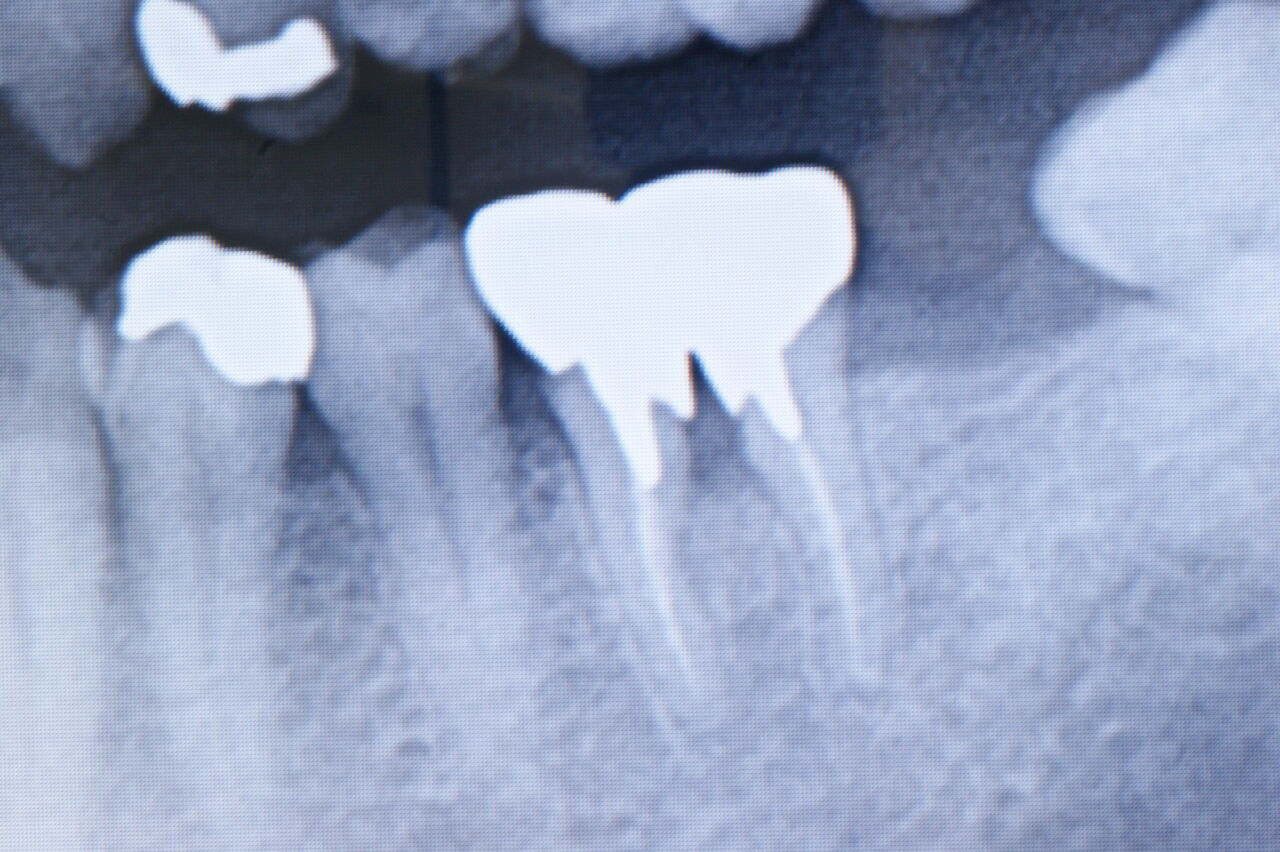

❸分割抜歯→インプラント:二本の根のうち一本を抜去後、そこに植立したインプラントと連結固定する方法。(17年経過)